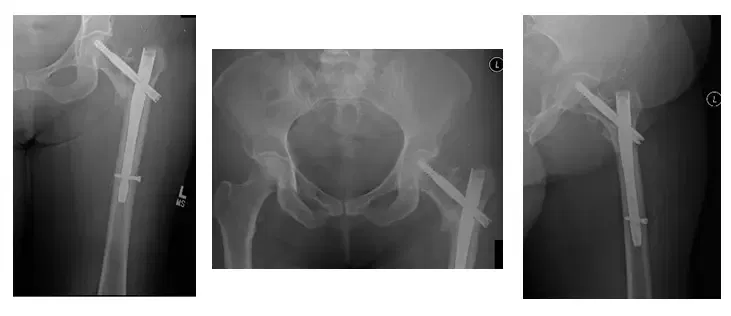

La paciente es una mujer de 75 años que acudió a nosotros con dolor intenso en la cadera izquierda tras someterse a una fijación interna de reducción abierta (ORIF) de la cadera izquierda. El paciente vino con radiografías para revisar, como se muestra a continuación,...